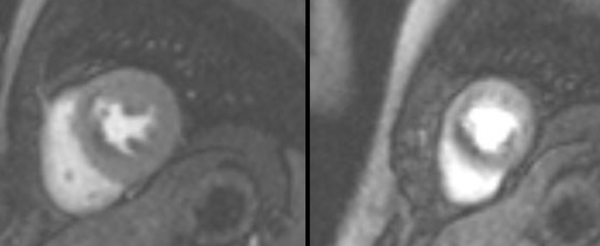

Hypertrophic Cardiomyopathy

Adenosine stress CMR can diagnosis microvascular ischemia/dysfunction in patients with hypertrophic cardiomyopathy